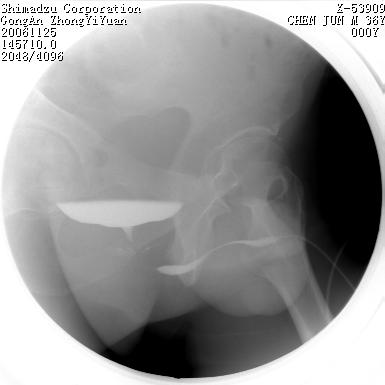

男 66岁 排尿困难半年;此人腹腔及腹膜后积液.

尿道充盈缺损,考虑占位.

后尿道内充盈缺损;前列腺结石。

后尿道狭窄,其中可见充盈缺损,我认为应先排除结核.

后尿路精阜水平充盈缺损,考虑结石或占位病变可能,建议mri检查,精阜水平尿路周围条索状密度增高影,考虑造影剂逆流入输精管或周围静脉。